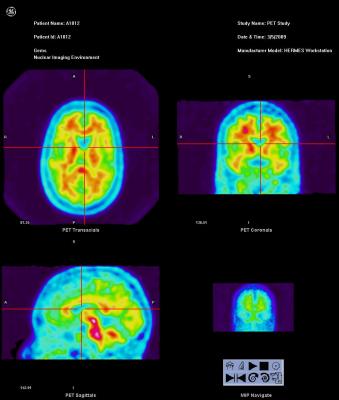

Vizamyl (flutemetamol F-18) uptake shown in brains of patients who are normal and full of amyloid plaque.

Vizamyl, flutemetamol, FDA, GE